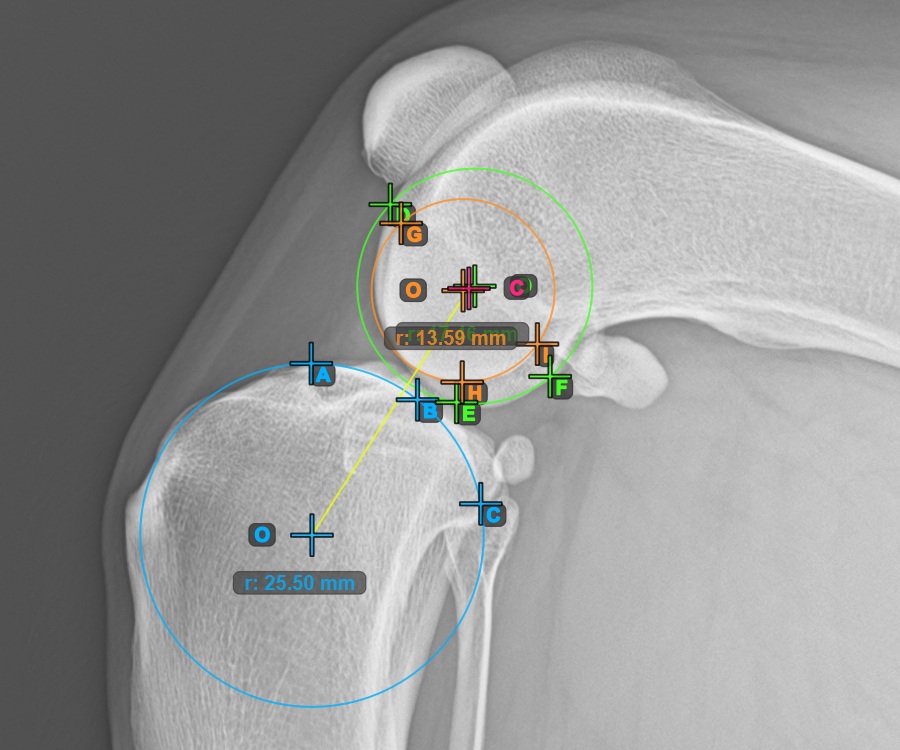

Mark one point in front of the joint on the common tangent between the two main condylus circles. A line will be drawn automatically through the marked point.

The image below represents a typical placement of the point on the common tangent between the two circles.